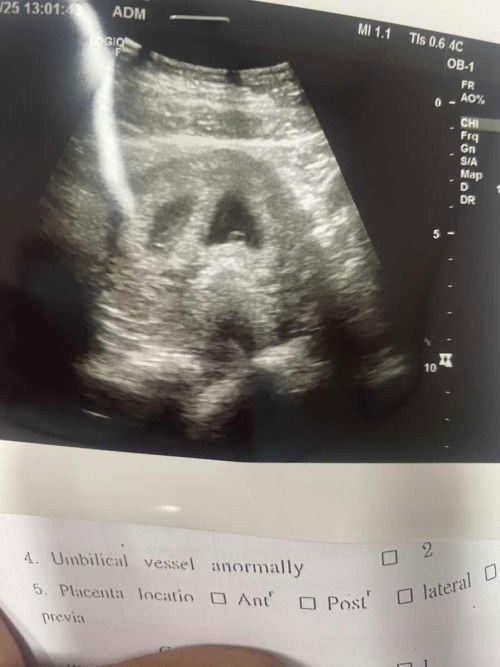

อยากให้แม่ๆช่วยดูหน่อยค่ะใช่น้องแฝดมั้ยคะ

หมอบอกอีก2อาทิตย์ไปซาวด์ดูอีกทีค่ะ